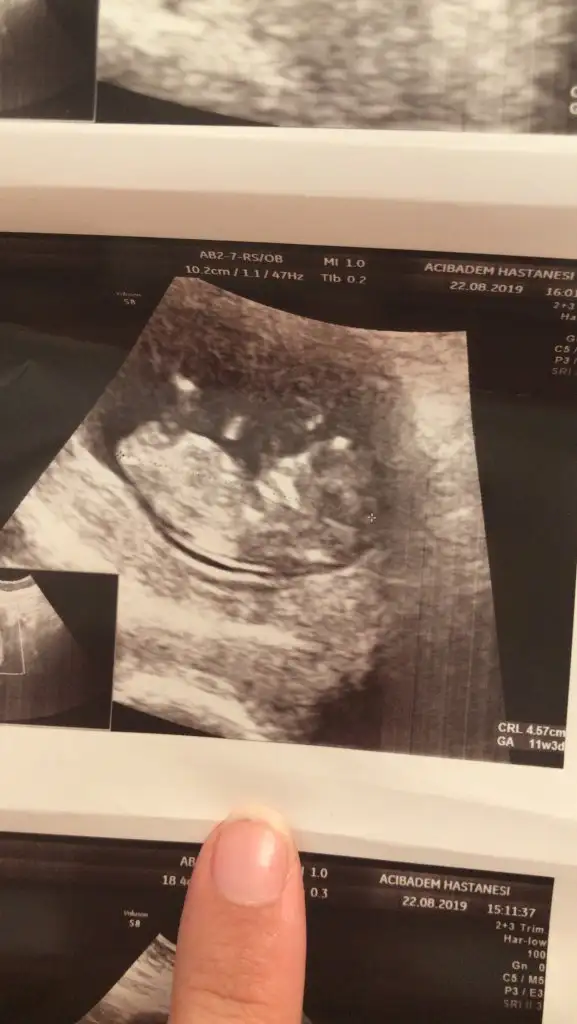

Saglıkla gelsin ler inşallahBenim de 1 kız 1 erkek gibi görünüyormuş tabi kesin değil ama tahmininiz doğru sanırımIkra meyra CocoChanelmademoiselle

15 haftadasınız kesin dirBenim de 1 kız 1 erkek gibi görünüyormuş tabi kesin değil ama tahmininiz doğru sanırımIkra meyra CocoChanelmademoiselle

Net olmamakla birlikte Kız gibi tam net degil başka usg varmıKızlar bu da arkadaşıma ait bi görüntü. 10+2. Tahminlerinizi merak ediyoruz

Bi tane daha var ama onda hiç belli değil en belirgin olanı buNet olmamakla birlikte Kız gibi tam net degil başka usg varmı

ErkekBanada tahmin yapın kızlaaar